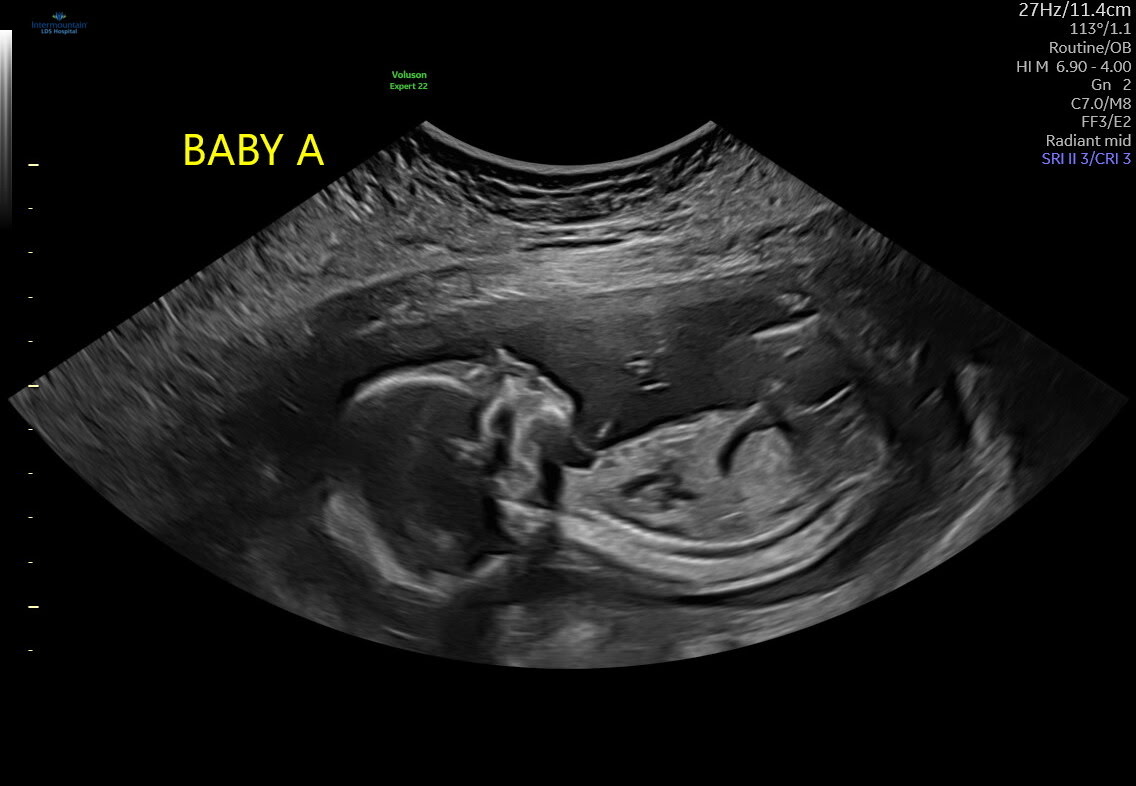

πΆπ Twin Baby Reveal ππΆ

Guess Baby A

Boy

Girl

π It's Twin Girls! π

πDue May 23, 2026π